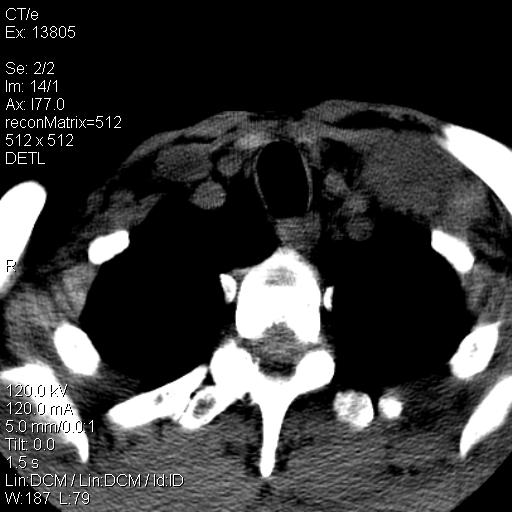

上腹部疼痛一月,呕吐10天,发现左侧颈部包快10天 胸部cr片未见明显异常。

左侧胸锁乳突肌下方、颈血管旁低密度肿块影,肿块密度尚均匀,边缘大部分清楚,邻近组织稍受压移位。考虑颈部神经鞘瘤可能性大。

颈部及腹膜后淋巴瘤可能性大

考虑1、淋巴瘤2、转移瘤